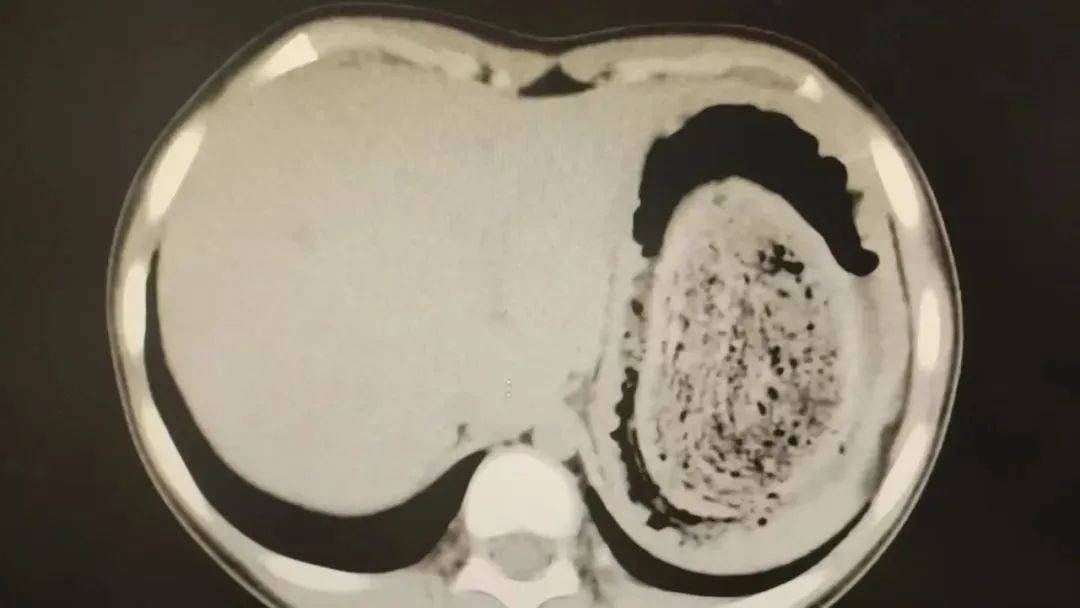

消化内科副主任医师陈琼发现,妮妮肤色惨白,甲床也是毫无血色皇冠信用网登2。血常规检查结果提示,孩子的血红蛋白仅59g/L,远低于正常值110g/L,属于重度贫血的状态,经过胃肠道超声检查,结果提示可能是“胃石症”。

在胃镜帮助下,妮妮胃里的情况逐渐明了皇冠信用网登2。一个滚圆黑色的毛发球混合着食物残渣占据整个胃腔,这些头发相互缠绕形成一个实心的“发石”,此外胃里还有一个鸡蛋大小的溃疡。

症结找到了,就是这个巨大的发石导致妮妮出现营养不良、贫血和闭经,当务之急就是取出“发石”,给胃进行“大扫除”皇冠信用网登2。

头发缠绕在一起十分坚硬,体积巨大,胃镜尝试多次均难以取出,医护人员不得不采取开放手术的方式来取“发石”皇冠信用网登2。

“发石”混杂着食物残渣,就像一个黑色的小西瓜皇冠信用网登2。由于整个“发石”体积太大,为避免损伤胃壁,医生借助手术工具将“发石”切割、分解,再小心翼翼地分块取出。整场手术持续2个多小时,最终取出4斤头发碎片。